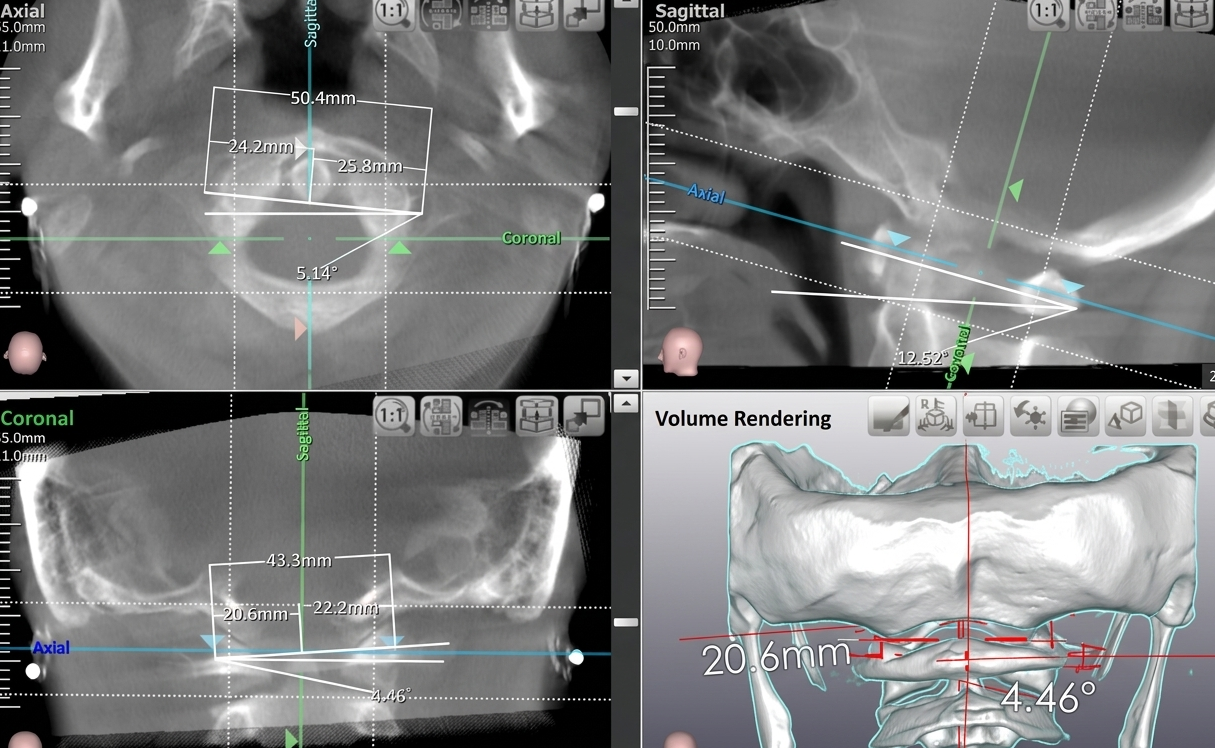

当オフィスがCT・レントゲンによる客観的な分析を必須とするのは、「0.1ミリの妨げ」すら正確に特定することができるためです。

CBCT・レントゲンを用いた科学的精密分析

感覚や経験に頼りきる施術は行いません。画像に基づいた正確な分析が、安全なケアの根拠です。

使用テクニック:Palmer HIO, Blair Upper Cervical (精密な画像による構造分析に基づく上部頸椎調整法)

安全で正確なケアを提供するため、初回時に一度だけ、当オフィス提携先クリニックにてCT・レントゲン撮影をお願いしております。 「感覚と経験」に頼りすぎない、科学的根拠に基づいた分析のための大切なステップです。

この画像データが、無駄な施術を省き、最短ルートで変化を出すための『設計図』となります。